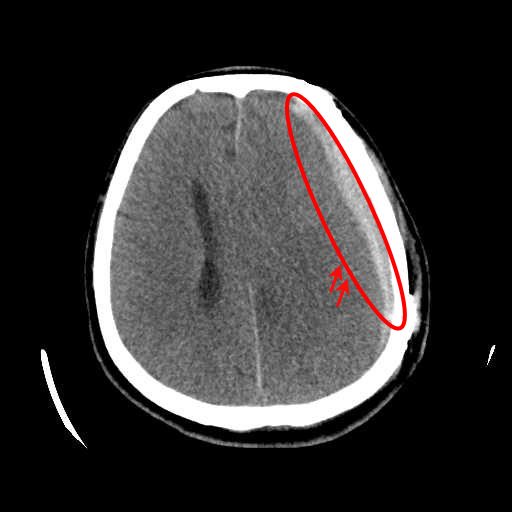

Figure 1: Illustrative examples of different types of brain hemorrhages in CT scans. The hemorrhagic regions are highlighted in red. (a) IPH, (b) IVH, (c) EDH, (d) SAH, (e) SDH.

The dataset used in this study was collected from two medical centers in Tehran, Iran: Rasoul Akram Hospital and Firouzabadi Hospital, over a period spanning 2018 to 2024. All CT scans were manually labeled hierarchically by two board-certified neurosurgeons to ensure accurate classification of ICH subtypes. The labeling process involved an initial annotation by one neurosurgeon, followed by validation and verification by a second expert to minimize errors and inconsistencies. Fig. 1 illustrates representative examples of different ICH subtypes in brain CT scans. The hemorrhagic regions are highlighted in red for better visualization. These annotated examples provide insight into the distinct imaging characteristics of each hemorrhage type, emphasizing the variability in their locations and appearances within the brain. The study received ethical approval, and data collection was conducted in compliance with institutional review board (IRB) regulations and the Declaration of Helsinki, ensuring patient confidentiality and adherence to ethical standards.